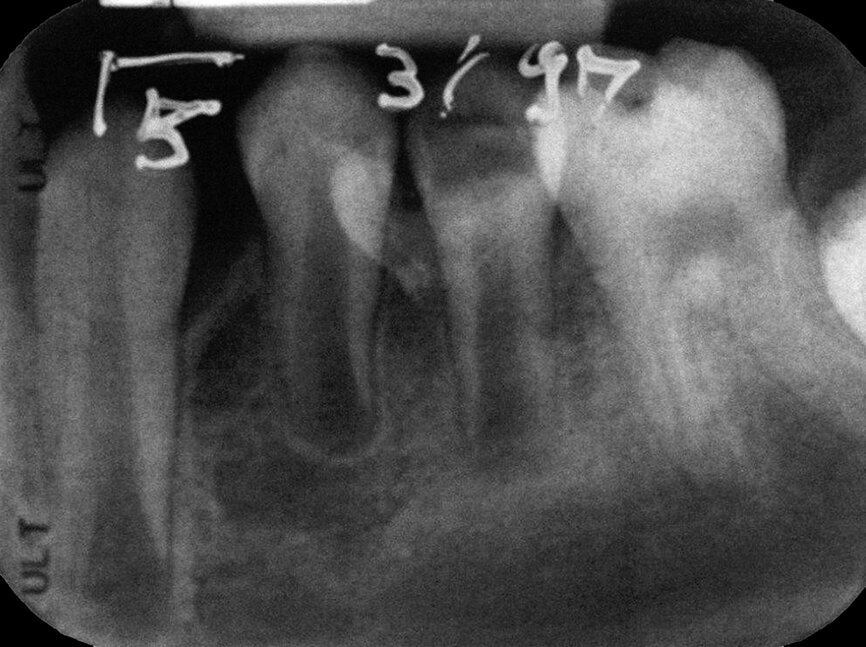

Case 2: Male (born 28 December 1980): Tooth 14

Fig. 4a: 18 August 1989 ante vitalextirpation.

Case 2: Male (born

28 December 1980): Tooth 14

Fig. 4b: 18 August 1989 post vitalextirpation.

Fig. 4c: 16 January 2004 status.